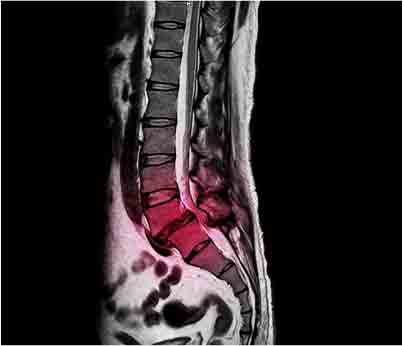

Patients may experience symptoms such as pain, numbness, and weakness in the lower back, pelvis, and legs. Some people may experience foot drop, loss of bowel and bladder control, sexual dysfunction, and paralysis. A medical emergency can result depending on the severity of these symptoms. People experiencing any of these symptoms should seek a consultation with a neurologist orneurosurgeon for an assessment that requires a magnetic resonance image (MRI) of the lumbar spine and a myelogram to assess damage to the spinal cord.

Yok_onepiece. (2020). [MRI Image]. A lateral projection of lumbar spine x-ray showing degenerativespondylolisthesis at L5/S1 level that causes low back pain and sciatica. https://www.shutterstock.com/image-photo/lateral-projection-lumbar-spine-xray-showing-1774387022